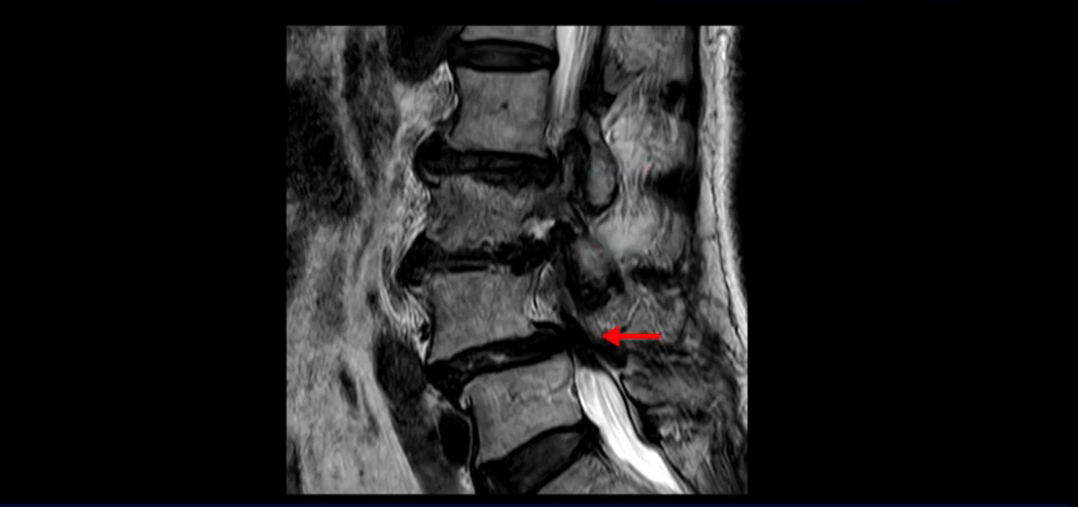

4번 5번에는 뼈가 밀려 나간 전방전위증도 있고,

또 척추관협착도 매우 심합니다.

척추관이 심하게 좁아져 있습니다.

이렇게 여러 마디가 안 좋고 뼈도 밀려 나가 있으니까 나사박는 수술해야 하는데, 대학병원에서도 수술을 한 번에 못 하고 두 번에 나눠서 해야 한다고 들으셨습니다. 왼쪽으로 신경가지가 빠져나가는 추간공도 많이 좁아져 있습니다.